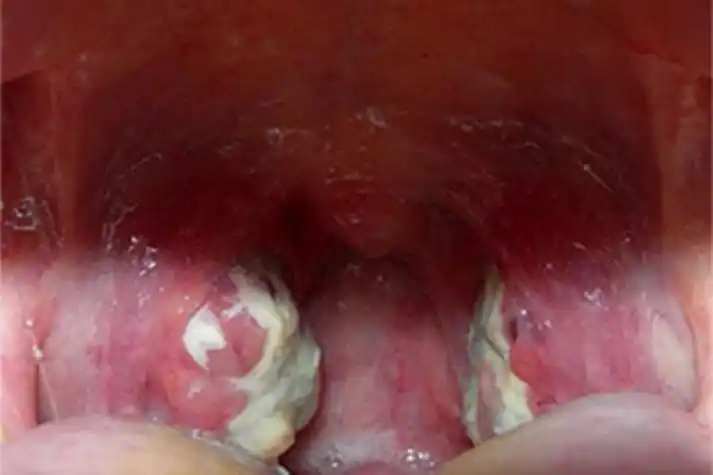

14,我儿子也经常扁桃体化脓发炎,严重的时候扁桃体上可以看见很多白色

中医儿科杨晓:小儿急性化脓性扁桃体炎的症状,原因,治疗及预防

急性化脓性扁桃体炎图

急性滤泡性扁桃体炎扁桃体症状图